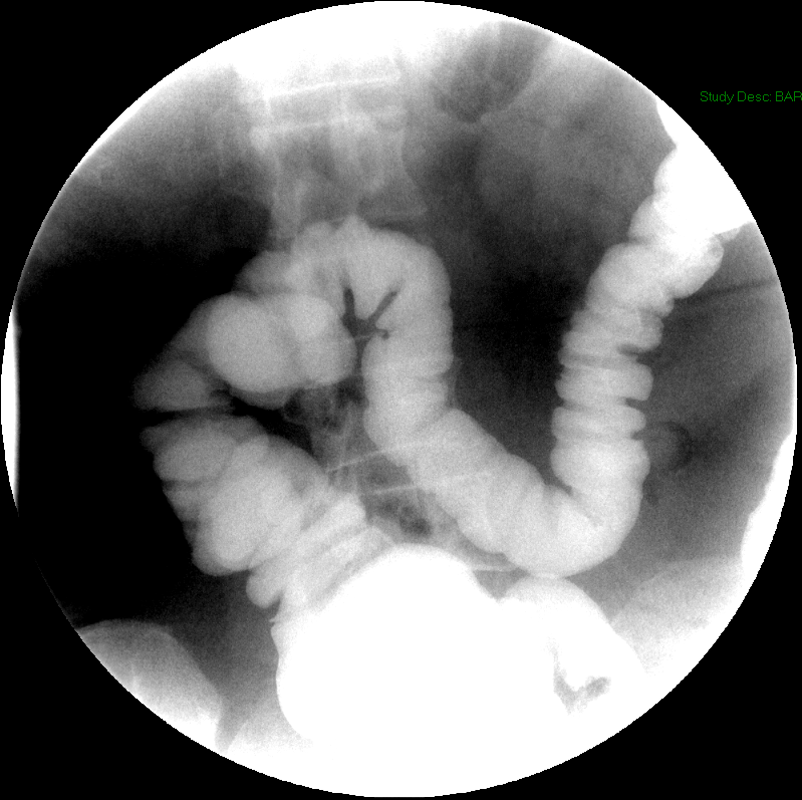

- Once the barium has reached the small bowel, you will go into the room and obtain spot images of the contrast material filled small bowel.

- Obtain images of the terminal ileum and the ileocecal valve filled with contrast material

(key image 6)

(key image 7)

(key image 8)

(key image 9)

(key image 10).

- Obtain spot images of the remainder of the small bowel

(key image 11)

(key image 12)

(key image 13)

(key image 14).

- Obtain images of all four quadrants. Use the compression paddle to separate loops of small bowel from each other.

- Evaluate for tethering of small bowel to any other structures.

- Observe for small bowel peristalsis.